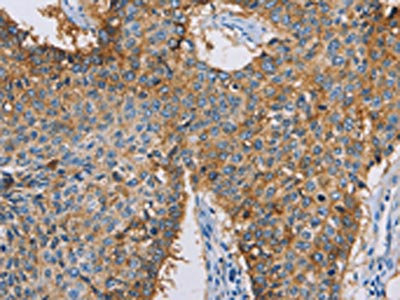

• The image on the left is immunohistochemistry of paraffin-embedded Human lung cancer tissue using CSB-PA251431(CDCP1 Antibody) at dilution 1/50, on the right is treated with synthetic peptide. (Original magnification: ×200)

• The image on the left is immunohistochemistry of paraffin-embedded Human thyroid cancer tissue using CSB-PA251431(CDCP1 Antibody) at dilution 1/50, on the right is treated with synthetic peptide. (Original magnification: ×200)